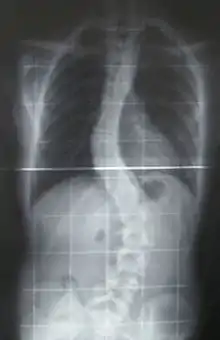

When scoliosis is suspected, weight-bearing, full-spine AP/coronal (front-back view) and lateral/sagittal (side view) X-rays are usually taken to assess the scoliosis curves and the kyphosis and lordosis, as these can also be affected in individuals with scoliosis. Full-length standing spine X-rays are the standard method for evaluating the severity and progression of scoliosis, and whether it is congenital or idiopathic in nature. In growing individuals, serial radiographs are obtained at 3- to 12-month intervals to follow curve progression, and, in some instances, MRI investigation is warranted to look at the spinal cord.[79] An average scoliosis patient has been in contact with around 50–300 mGy of radiation due to these radiographs during this time period.[80]

The standard method for assessing the curvature quantitatively is measuring the Cobb angle, which is the angle between two lines, drawn perpendicular to the upper endplate of the uppermost vertebra involved and the lower endplate of the lowest vertebra involved. For people with two curves, Cobb angles are followed for both curves. In some people, lateral-bending X-rays are obtained to assess the flexibility of the curves or the primary and compensatory curves.